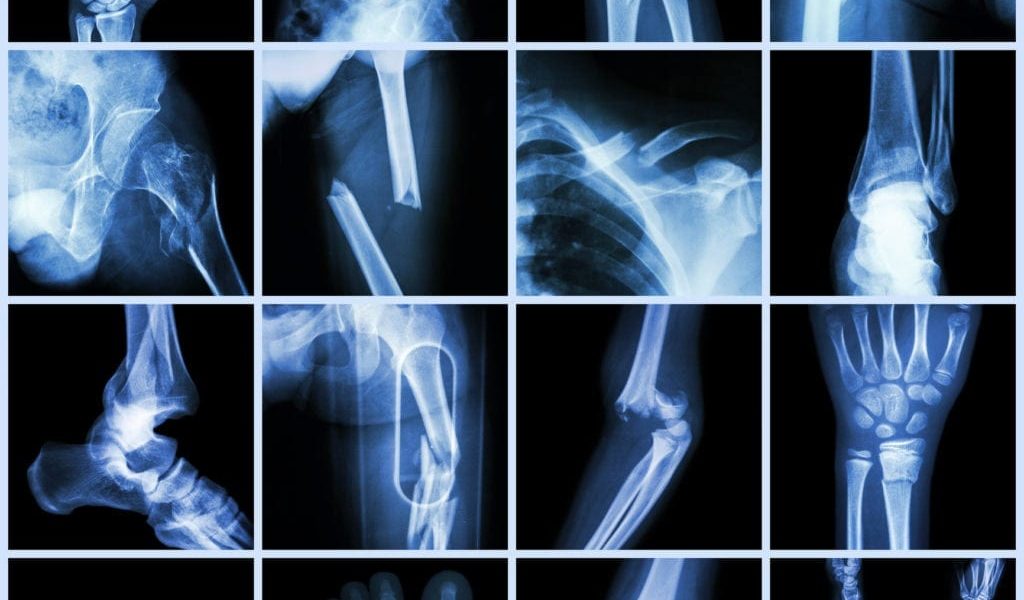

For an ankle fracture to fully heal, the joint must be stable and the only way to determine this is with x-rays.

Ankle fractures will depend on the area of the fracture. This is another reason you should always seek advice from a podiatrist to know the extent and location of the ankle fracture.